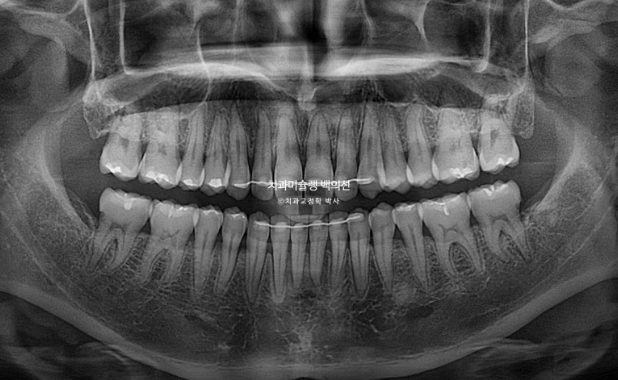

1년간의 치료기간 동안 치근흡수는 없고 뿌리 평행도는 좋습니다